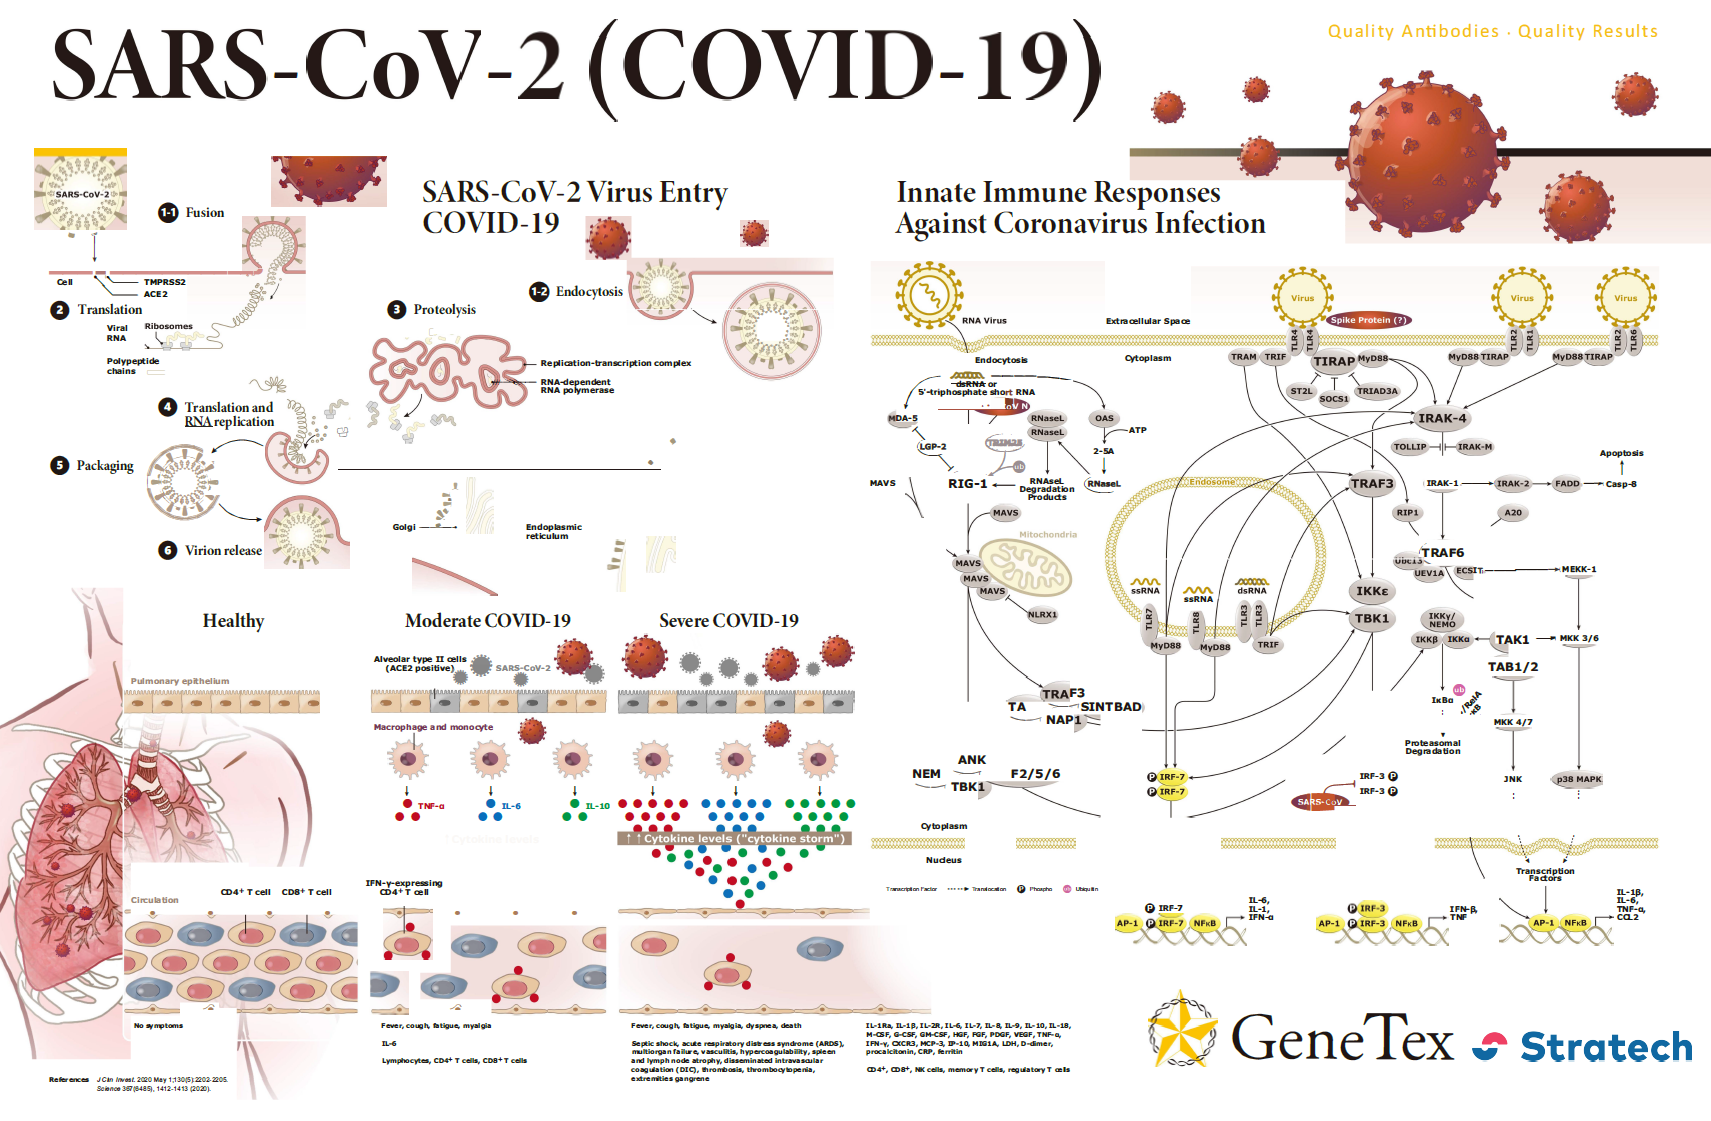

| Spike (S) | Spike full-length (~1273 a.a. in SARS-CoV-2) protein precursor is cleaved into glycosylated subunits, S1 and S2 (S2’). S1 binds to the host’s receptor, ACE2, while S2 mediates viral and host membrane fusion. | 1 |

| Nucleocapsid (N) | Nucleocapsid (~419 a.a. in SARS-CoV-2) binds viral genomic RNA and forms a helical ribonucleocapsid. Involved in genome protection, viral RNA replication, virion assembly, and immune evasion. Interacts with M and nsp3 proteins. | 2 |

| Membrane (M) | Membrane/matrix protein (~222 a.a. in SARS-CoV-2) is the most abundant structural component of the virion, and very conserved. Mediates assembly and budding of viral particles through recruitment of other structural proteins to “ER-Golgi-intermediate compartment (ERGIC)”. Interaction with N for RNA packaging into virion. Interacts with accessory proteins 3a and 7a. Mitigation of immune response? | 3 |

| Envelope (E) | Envelope small membrane protein (~75 a.a. in SARS-CoV-2) is a single-pass type III membrane protein involved in viral assembly, budding, and pathogenesis. Localizes to ERGIC. Forms a homopentameric ion channel and is a viroporin. Interacts with M, N, 3a, and 7a. | 4 |

| ORF3a | ORF3a (~275 a.a. in SARS-CoV-2) is a multi-pass membrane protein that forms a homotetrameric viroporin in SARS-CoV. It interacts with accessory protein 7a, M, S and E. May be involved in viral release. Importantly, it also activates both NF-kB and NLRP3 inflammasome and contributes to the generation of cytokine storm. | 16 |

| ORF6 | ORF6 (~61 a.a. in SARS-CoV-2) appears to be a virulence factor in SARS-CoV. It was shown to be an antagonist of type I interferons (IFNs) and is involved in viral escape from the host innate immune system. | 17 |